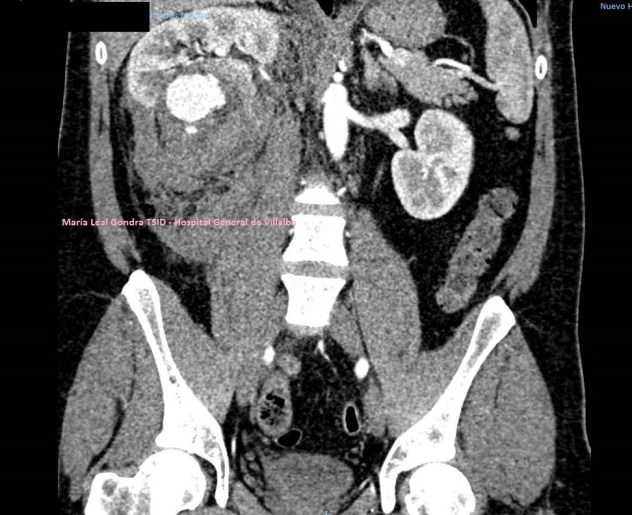

Se realiza Tc con contraste para completar estudio de extensión, en el que se confirman los hallazgos visualizados en la ecografía incluido el nódulo metastásico umbilical (FIGURA 8).

8